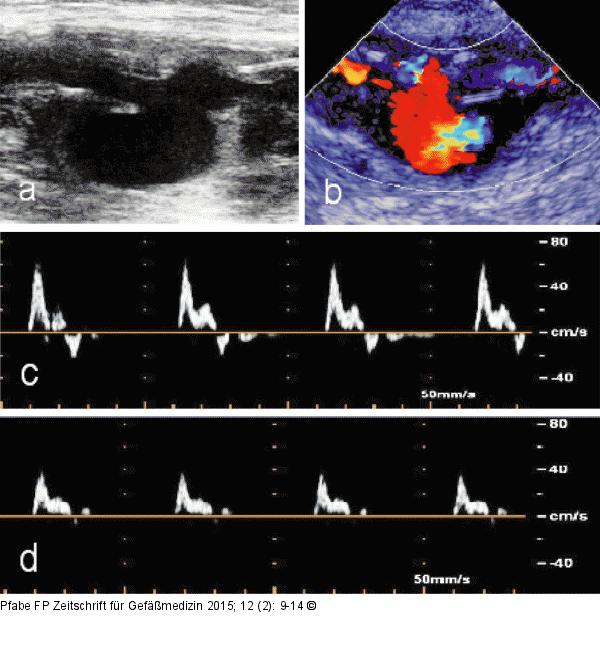

Abbildung 2a-d: Bypass-Ruptur Duplexsonographische Diagnostik. (a): Bypass-Ruptur mit Dehiszenz der Rupturränder im B-Mode (Pfeil); (b): Pseudoaneurysma nach gedeckter Bypass-Ruptur im Color-Mode; (c): PW-Dopplersignal proximal der Ruptur; (d): PW-Dopplersignal distal des pulsierenden Hämatoms. |

Duplexsonographische Diagnostik. (a): Bypass-Ruptur mit Dehiszenz der Rupturränder im B-Mode (Pfeil); (b): Pseudoaneurysma nach gedeckter Bypass-Ruptur im Color-Mode; (c): PW-Dopplersignal proximal der Ruptur; (d): PW-Dopplersignal distal des pulsierenden Hämatoms. |